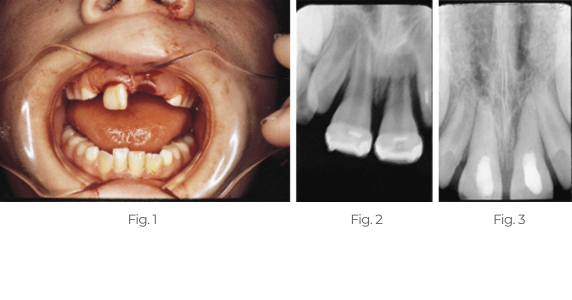

Treatment of Avulsed Tooth

This child presented with avulsed left central and traumatized right central incisors. Two weeks after replantation and splinting, the pulps were removed and Pulpdent Paste was placed in the root canals. The case was followed regularly for 12 months, and the Pulpdent Paste was changed at each visit. After one year, the root canals were obturated with Pulpdent Root Canal Sealer using the Pressure Syringe technique.

Fig. 1: Photo shows child with avulsed left central and traumatized right central incisor.

Fig. 2: Radiograph taken two weeks following replantation shows replanted tooth, open apices and bone loss. At this visit the root canals were negotiated and Pulpdent Paste was placed as a dressing to stimulate healing and discourage traumatic rejection (not shown).

Fig. 3: Radiograph taken one year after treatment shows Pulpdent Paste in the root canals, apexification and bone fill.